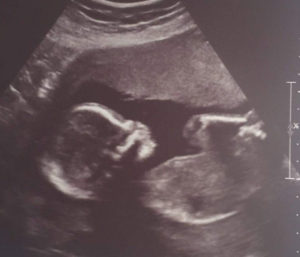

canadian-mom-pregnant-quickly-after-tubal-reversalI am currently 20 weeks with a baby girl.

We are still shocked at how quickly we conceived!